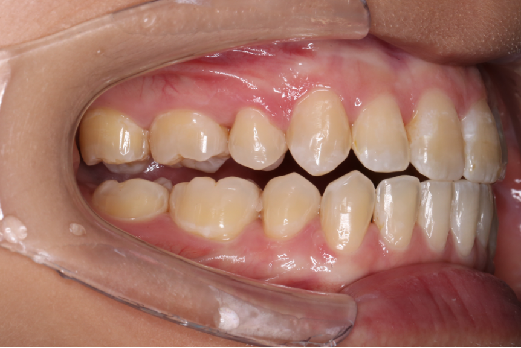

• 磨牙,尖牙I类关系,中线齐

• 上下牙列中度拥挤

• 上下前牙唇倾

IntraoralExamination(2016-08.31,Wu)

2018.11.14  术后磨牙尖牙I类关系,中线齐,覆合,覆盖正常